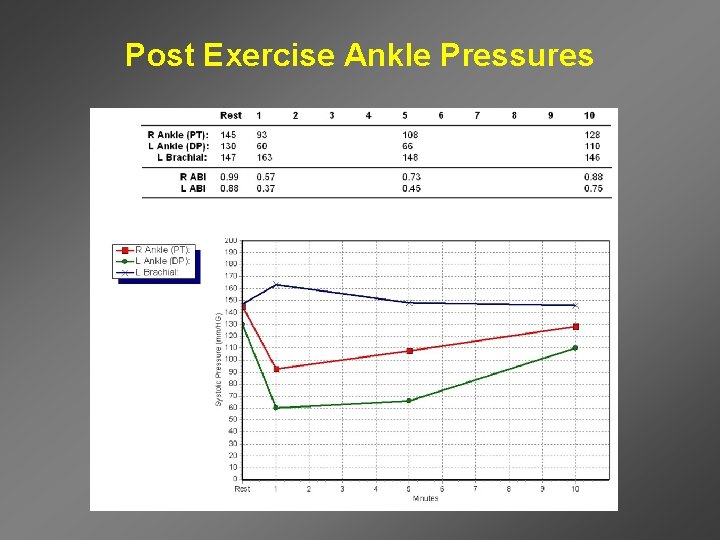

Post Exercise Ankle Pressures